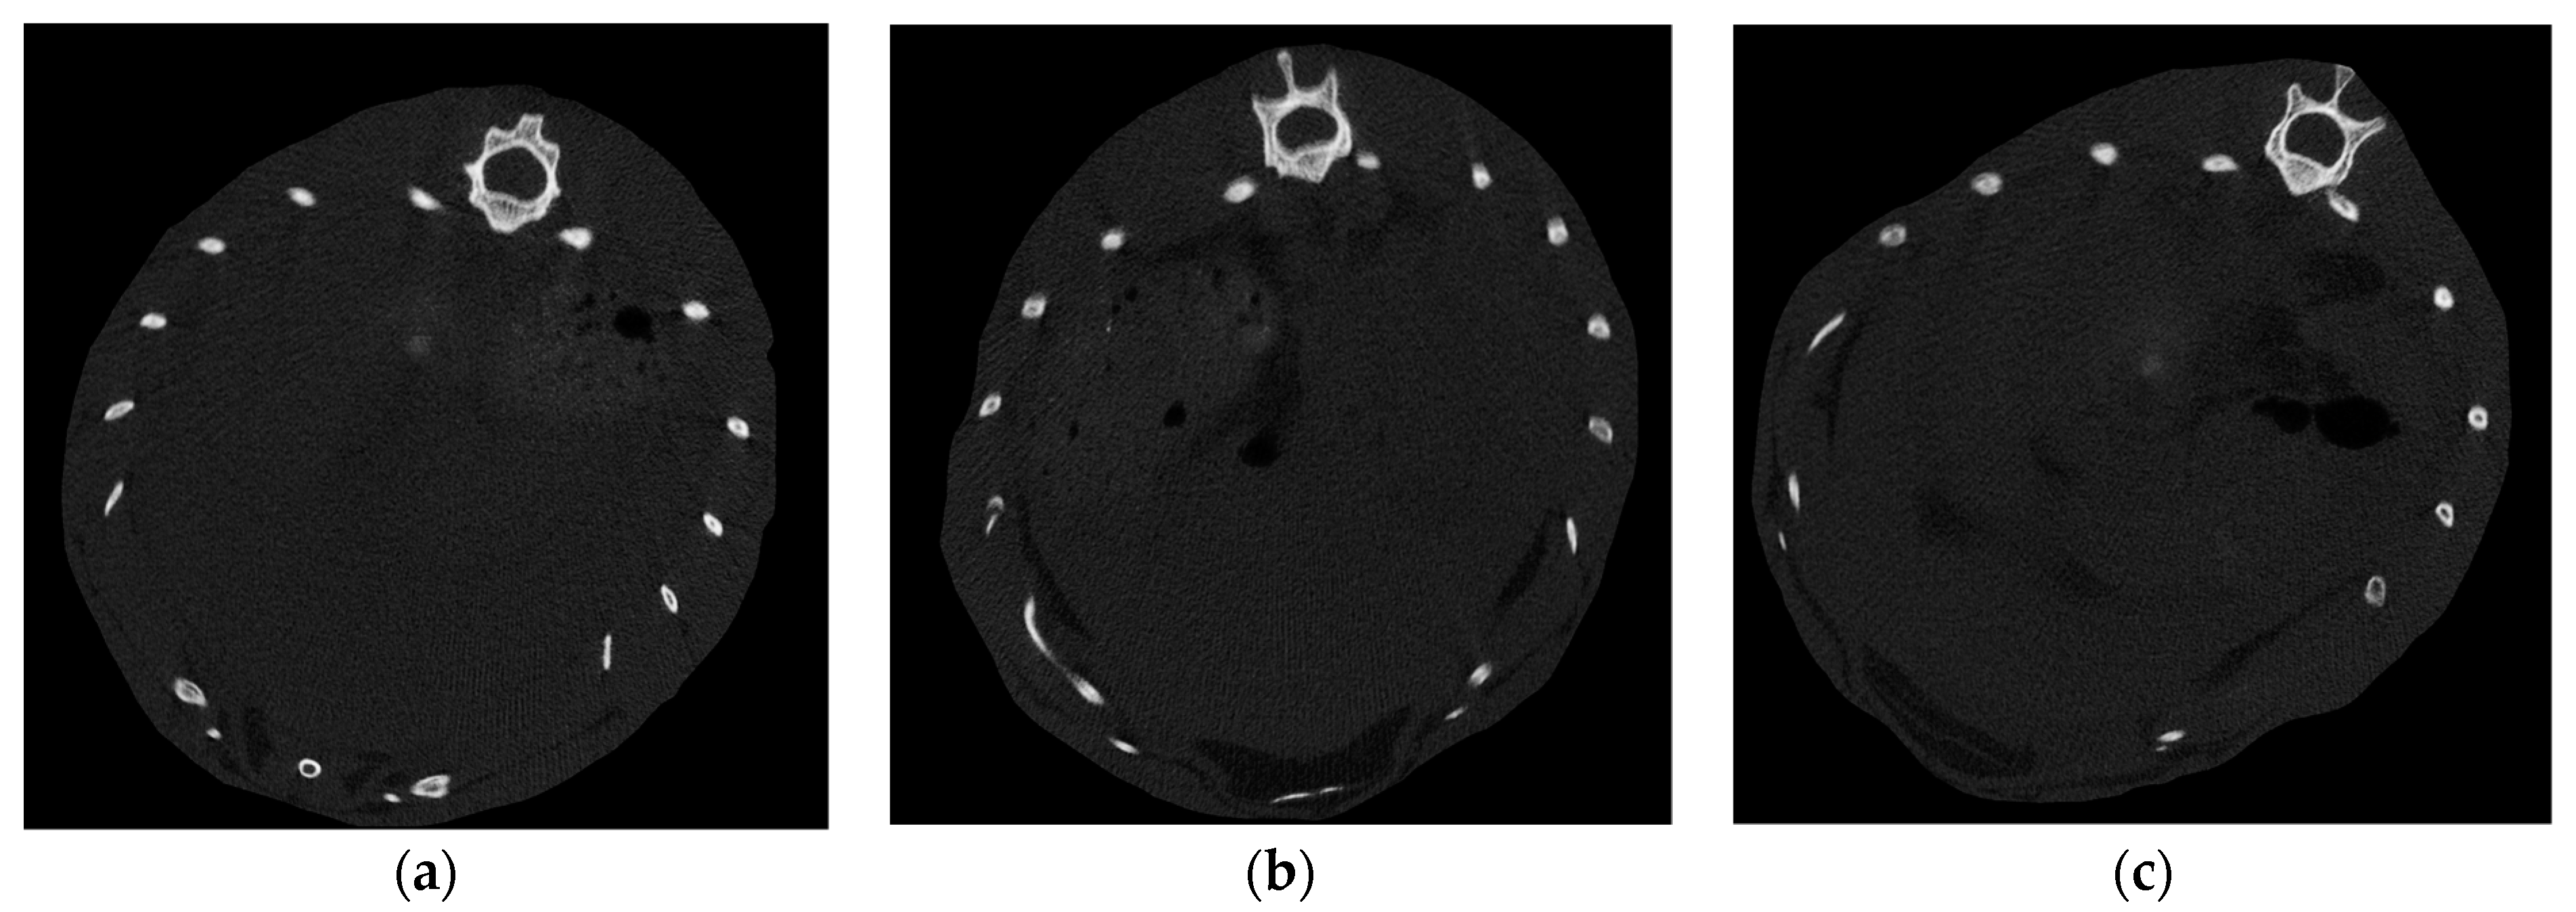

3.1.3. Micro-CT Scan